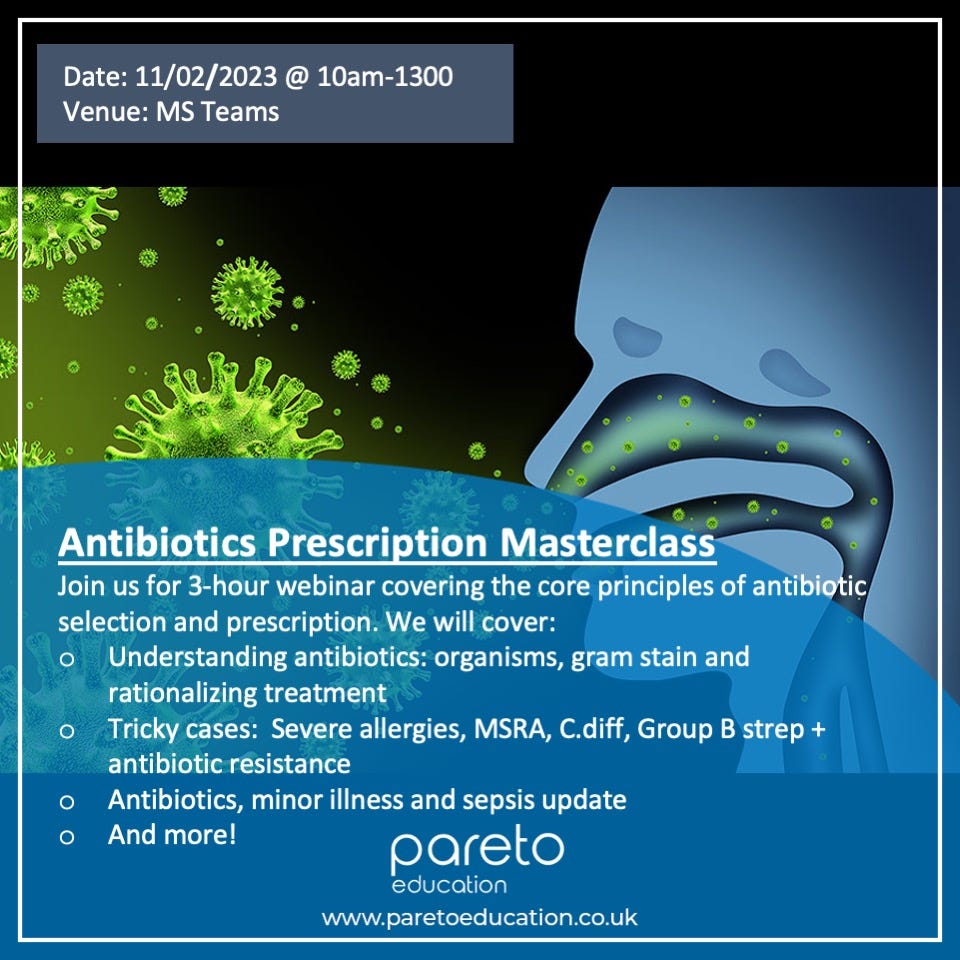

For example, we at Pareto are aware that practices are encouraged to have better antibiotics stewardship and are rewarded for reducing the amount of unnecessary antibiotic prescriptions. Practices are always after staff who are experienced prescribers and can make better informed decisions about antibiotic prescribing. It is for this reason we have organised a CPD accredited antibiotic masterclass to explain some key principles concerning antibiotic prescribing and stewardship. If you’re interested, you can book on here. Demonstrating training on antibiotic selection and prescription on your CV is sure to impress your current employer or any future employer you may encounter.